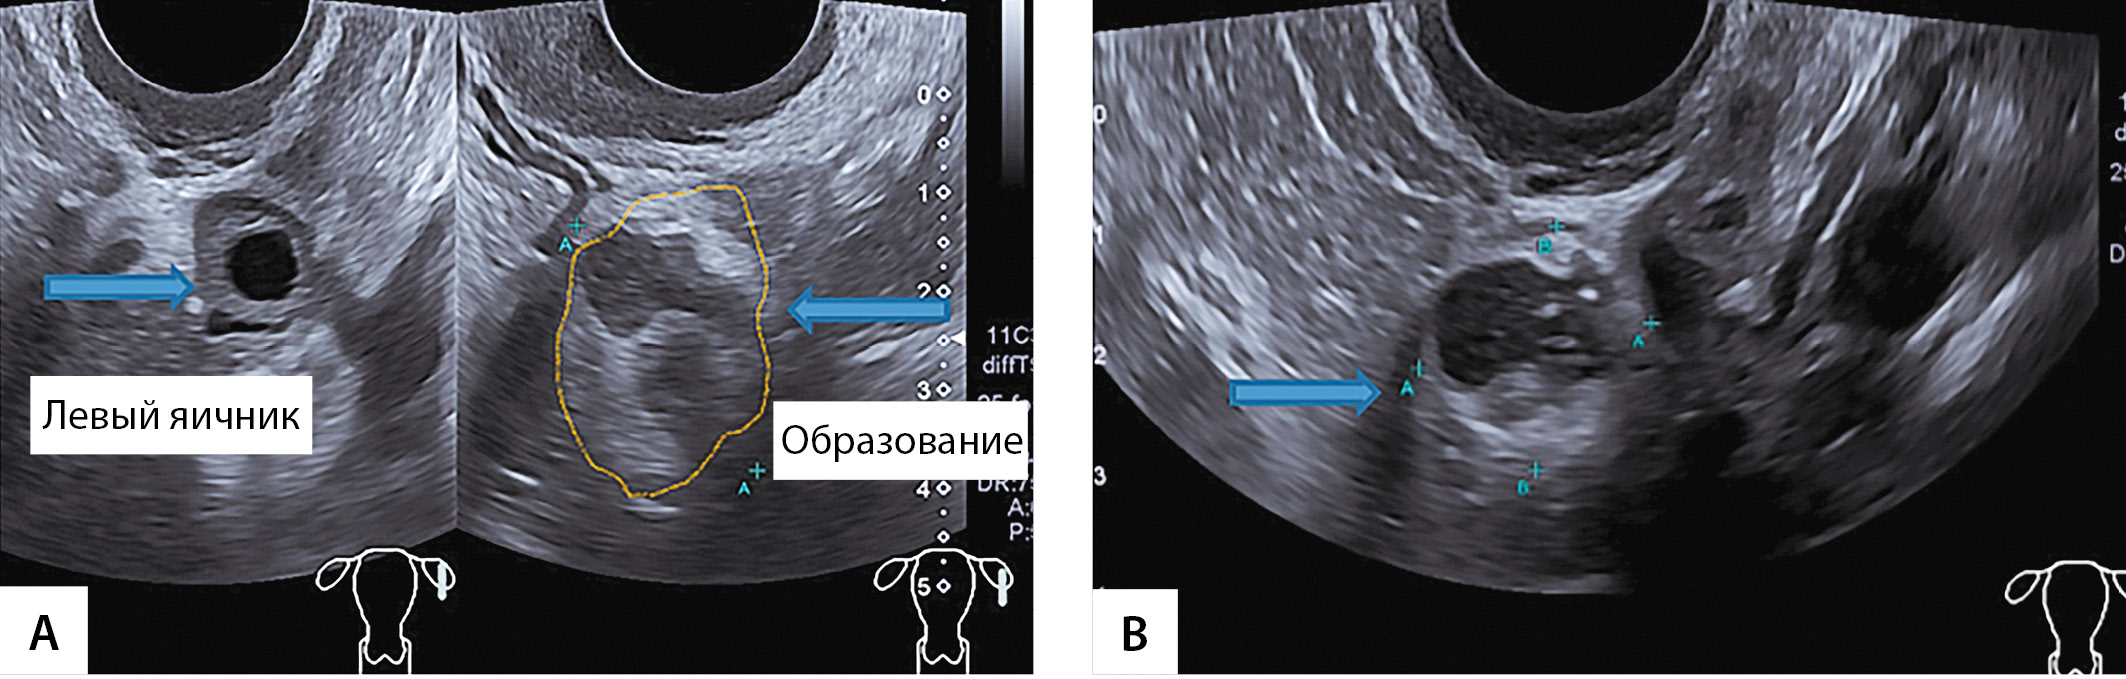

4. Figure 3. Echograms of ultrasound examination of the left ovary and adjacent formation (OART): A - arrows indicate the left ovary with a follicle and formation (OART); B - ultrasound picture of the formation adjacent to the left ovary (hyperechoic peripheral part, hypoechoic central part). | |